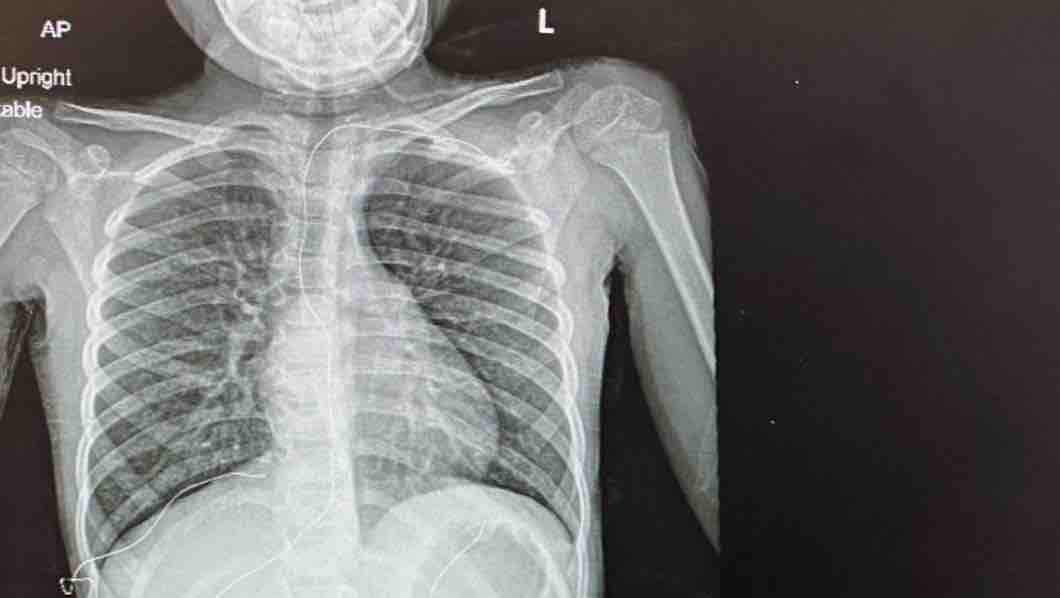

Yo, Monica Longo De Jesus, soy una madre con tres hijos que criar, y en este momento estoy pasando por el peor momento de mi vida y de mi hijo también. Mi hijo Nathan Piñeiro Longo, de 10 años, tiene asma crónica desde que nació. Ha sido una lucha toda su vida. Se ha visto limitado a hacer cosas normales de niños debido a su condición. Incluso afectando su rendimiento académico, no puede hacer la clase de educación física porque se queda sin aire rápidamente. Entrando y saliendo de hospitalizaciones constantemente debido a los ataques de asma y su respiración. Este año ha estado hospitalizado en más de cinco ocasiones donde ha tenido que permanecer en el hospital un mínimo de tres días conectado a una máquina de oxígeno. A principios de año su médico me dio la noticia de que ninguna madre debería oír ni pasar un niño. Mi hijo puede que necesite un trasplante de pulmón todavía no es seguro primero tenemos que pasar por unos estudios que determinarán el que va a pasar. Su pulmón izquierdo ya no responde a ningún tratamiento. Los médicos quieren mantenerlo hospitalizado con oxígeno hasta que puedan encontrar una solución a su condición adicional a un trasplante de pulmón porque no tengo dinero para comprar un tanque de oxígeno o pagar las recargas o para los medicamentos necesarios. El seguro no lo cubrirá porque aparentemente para ellos su caso no es lo suficientemente malo como para cubrir el tanque de oxígeno, pero es lo único que lo ayuda a respirar mejor. Nathan no quiere estar en un hospital las 24 horas del día, los 7 días de la semana, alejado de sus hermanas y familiares. Estoy luchando para pagar mis cuentas en este momento. Es difícil para mí pagar todos los gastos médicos de mi casa. Nunca pensamos que pasaríamos por esto. No tengo el dinero para comprarlo yo solo. Con mucha esperanza, estoy escribiendo esta carta de recaudación de fondos para buscar su apoyo financiero. Le agradecería que contribuyera a la cirugía de mi hijo y me ayudara a darle una nueva vida. Cualquier donación será apreciado considerablemente. Dios te bendiga y gracias.

I, Monica Longo De Jesus, am a mother with three children to raise, and right now I am going through the worst moment of my life and that of my son as well. My son Nathan Piñeiro Longo, 10 years old, has had chronic asthma since he was born. It's been a struggle all his life. He has been limited to doing normal children's things due to his condition. Even affecting his academic performance, he cannot do the physical education class because he runs out of air quickly. Constantly entering and leaving hospitalizations due to asthma attacks and breathing. This year he has been hospitalized on more than five occasions where he has had to stay in the hospital for at least three days connected to an oxygen machine. At the beginning of the year her doctor gave me the news that no mother should hear or pass a child. My son may need a lung transplant. It's still not safe. First we have to go through some studies that will determine what will happen. Your left lung no longer responds to any treatment. Doctors want to keep him hospitalized with oxygen until they can find a solution to his condition in addition to a lung transplant because I don't have money to buy an oxygen tank or pay for refills or for the necessary medications. The insurance will not cover you because apparently for them your case is not bad enough to cover the oxygen tank, but it is the only thing that helps you breathe better. Nathan doesn't want to be in a hospital 24 hours a day, 7 days a week, away from his sisters and relatives. I'm struggling to pay my bills right now. It's hard for me to pay all the medical expenses of my house. We never thought we would go through this. I don't have the money to buy it myself. With a lot of hope, I am writing this fundraising letter to seek your financial support. I would appreciate it if you contributed to my son's surgery and helped me give him a new life. Any donation will be appreciated considerably. God bless you and thank you.

I, Monica Longo De Jesus, am a mother with three children to raise, and right now I am going through the worst moment of my life and that of my son as well. My son Nathan Piñeiro Longo, 10 years old, has had chronic asthma since he was born. It's been a struggle all his life. He has been limited to doing normal children's things due to his condition. Even affecting his academic performance, he cannot do the physical education class because he runs out of air quickly. Constantly entering and leaving hospitalizations due to asthma attacks and breathing. This year he has been hospitalized on more than five occasions where he has had to stay in the hospital for at least three days connected to an oxygen machine. At the beginning of the year her doctor gave me the news that no mother should hear or pass a child. My son may need a lung transplant. It's still not safe. First we have to go through some studies that will determine what will happen. Your left lung no longer responds to any treatment. Doctors want to keep him hospitalized with oxygen until they can find a solution to his condition in addition to a lung transplant because I don't have money to buy an oxygen tank or pay for refills or for the necessary medications. The insurance will not cover you because apparently for them your case is not bad enough to cover the oxygen tank, but it is the only thing that helps you breathe better. Nathan doesn't want to be in a hospital 24 hours a day, 7 days a week, away from his sisters and relatives. I'm struggling to pay my bills right now. It's hard for me to pay all the medical expenses of my house. We never thought we would go through this. I don't have the money to buy it myself. With a lot of hope, I am writing this fundraising letter to seek your financial support. I would appreciate it if you contributed to my son's surgery and helped me give him a new life. Any donation will be appreciated considerably. God bless you and thank you.